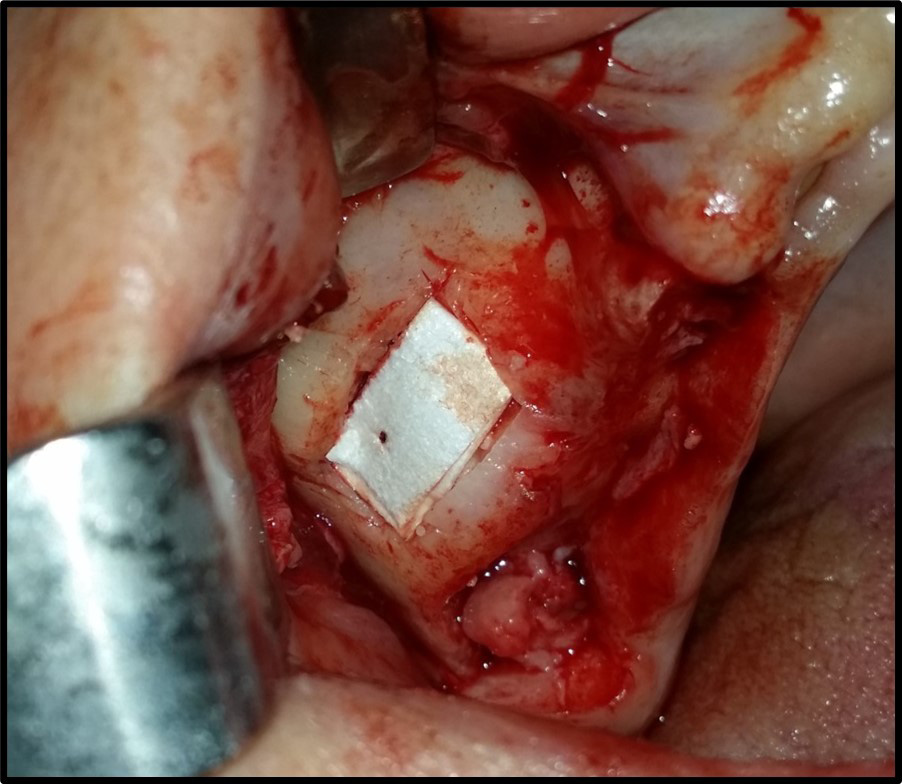

The sinus membrane was elevated with a sinus lift tool – the Dentium Advanced Sinus Kit (DASK) (Dentium, Cypress, USA), and for the grafting of the maxillary sinus, the mixture of CS or TCP with A-PRF was used (Figure 5). When using the TCP/A-PRF compound, we placed a collagen membrane on the bony window (Figure 6). The CS/A-PRF compound does not require any membrane, as a catalyst is added to the CS graft to harden fast. As such, the CS graft replaces the membrane due to its hardening and slow absorption properties.15

After maxillary sinus grafting, the bony window was covered with an absorbable collagen membrane on the side grafted with the TCP/A-PRF compound, which helps to prevent the surrounding connective tissue cells from entering the bone graft material and increases vital bone formation.24 No membrane was used for the CS/A-PRF compound, and the window was covered only with the CS graft material. The material can be used as a membrane due to its physical properties,15 which reduces the financial cost and the surgical procedure time.